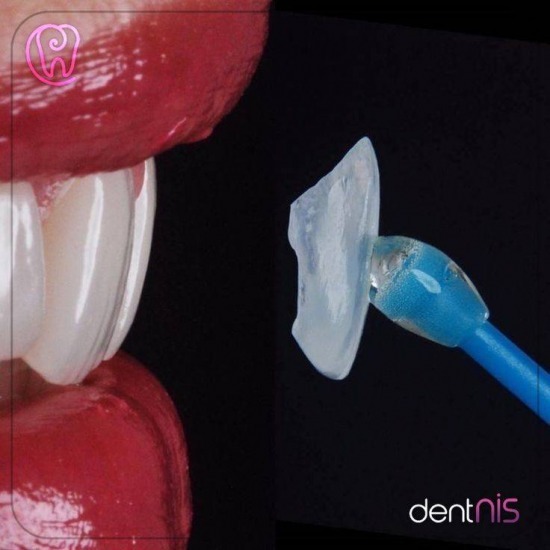

จัดฟันแบบมองไม่เห็น จัดฟันเสร็จเร็ว ฟันเคลื่อนเร็วมาก จัดฟันAI จัดฟันด้านใน จัดฟันแบบใหม่ จัดฟันแบบใหม่วางแผนด้วยระบบ AI ครั้งแรกในเอเชีย Brava คืออะไร Brava by Brius เป็นระบบจัดฟันแบบติดเครื่องมือด้านใน ด้วยเครื่องมือที่ออกแบบเฉพาะบุคคล วางแผนด้วยระบบAI ข้อดีของการจัดฟันBrava by BRIUS มองไม่เห็นเครื่องมือจัดฟัน เพราะเครื่องมืออยู่ด้านในทำให้ยิ้มได้อย่างมั่นใจ ใช้ระยะเวลาในการรักษาสั้นกว่าการจัดฟันรูปแบบอื่น ไม่มีปัญหาเรื่องจำนวนชั่วโมงที่ใส่เครื่องมือ เพราะเป็นเครื่องมือแบบติดแน่น ไม่ต้องคอยถอดและใส่ สามารถแปรงฟันและใช้ไหมขัดฟันได้ตามปกติ เพราะ ไม่ต้องพบทันตแพทย์บ่อย การจัดฟันแบบ Brava by BRIUS เหมาะสำหรับใครบ้าง? ผู้ที่ไม่ต้องการให้คนอื่นสังเกตเห็นเครื่องมือจัดฟัน ผู้ที่ต้องการเห็นผลลัพธ์การจัดฟันอย่างรวดเร็ว ในระยะเวลาไม่ถึงหนึ่งปี ผู้ที่ต้องการความสะดวกสบายในการใช้ชีวิต ไม่ต้องพกเครื่องมือติดตัว ไม่ต้องคอยนับชั่วโมงการใส่ นักเรียนโรงเรียนประจำหรืออยู่ต่างประเทศไม่ได้กลับมาประเทศไทยบ่อย ผู้ที่ไม่สะดวกมาปรับเครื่องมือบ่อย ๆ แนะนำคลินิกถอนฟัน ย่านบางแสน "คลินิกทันตกรรมเด็นทัลวิลลา" ที่ตั้งคลินิกทันตกรรมเด็นทัลวิลลา : 36/8 ถนนเนตรดี ตำบลแสนสุข อำเภอเมืองชลบุรี ชลบุรี 20130 เบอร์โทรติดต่อ : 09-6880-6805, 038-391-963